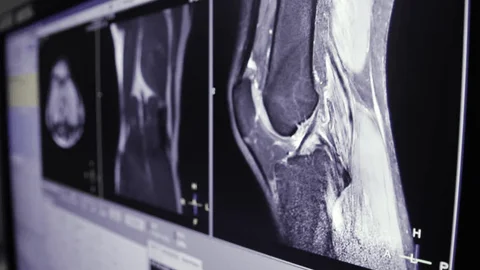

- Interpretation of the MRI findings